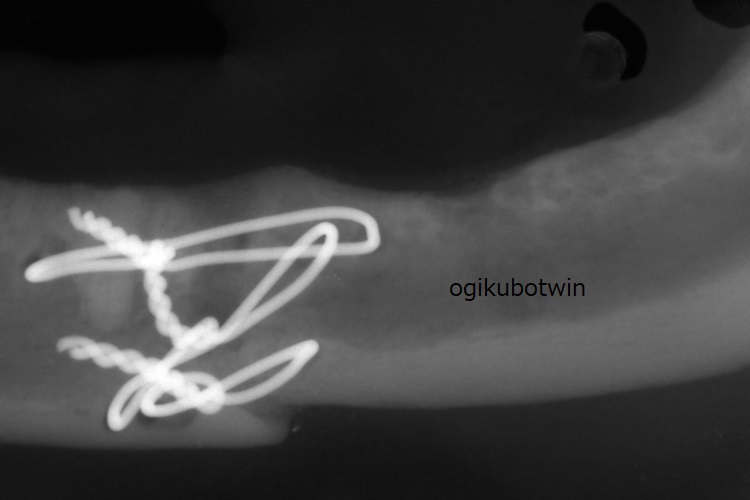

骨折治療から5か月後、顎の動揺は消失。歯科レントゲンでも骨折部の癒合が確認できました。

骨折が治癒したので全身麻酔下にて歯周病治療と骨内ワイヤーの抜去を行いました。

半年後の骨折部位の検診では、ワイヤーを通していた穴も塞がり経過は良好です。